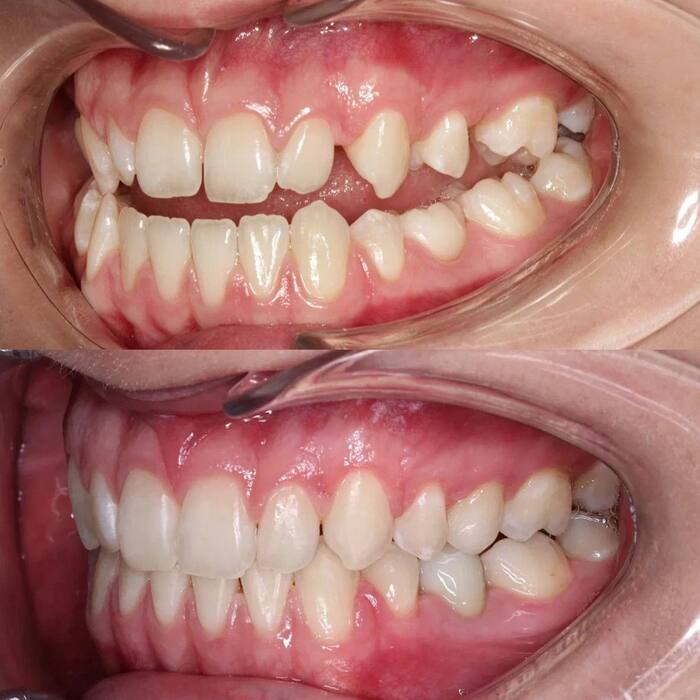

Проблема:

-Дисфункция височно-нижнечелюстного сустава

-Мезиальная окклюзия (выступание нижней челюсти вперед)

-Открытый прикус

-Сужение верхнего зубного ряда

-Ретенция зубов 1.5, 2.5 (непрорезавшиеся зубы)

-Первичная адентия 3.5 (отсутствие зачатка постоянного зуба)

Решение: лечение дисфункции сустава с последующим ортодонтическим на брекет-системе

Этапы лечения: миорелаксирующая каппа на 3 мес (сплинт-терапия). Далее ортодонтическое лечение на брекет-системе

В результате:

Нормализовали прикус пациентки, добились правильного смыкания зубов.

Сопоставили центральные линии верхнего и нижнего зубных рядов, получив красивый, а главное, функциональный результат.